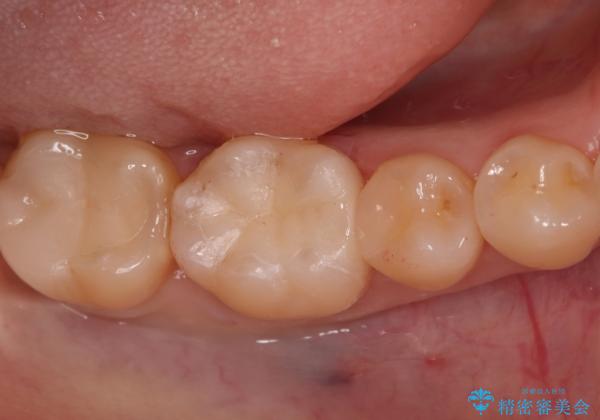

- 右下6番の奥歯に入っている金属の詰め物(メタルインレー)を気にされてご来院されました。お口の中の金属をなくしたいという患者様のご希望と、見た目の改善を目指し、天然歯に近い色と質感を持つセラミックインレーに交換する治療計画を立案しました。これにより、審美性の向上と、金属アレルギーのリスクがないメタルフリーの環境を実現することを目指しました。

治療では、まず古い金属のインレーを慎重に取り外し、内部に虫歯の再発がないかを丁寧に確認しました。歯を最小限だけ形成した後、精密な型取りから患者様の歯の色に合わせたオーダーメイドのセラミックインレーを作製しました。セラミックは、歯質との適合性が高く、プラークが付着しにくいため、虫歯の再発リスクを抑えるメリットもあります。適合性の高いセラミックインレーを装着することで、長年のコンプレックスだった銀歯がなくなり、機能的にも安定した自然な奥歯を取り戻していただけました。